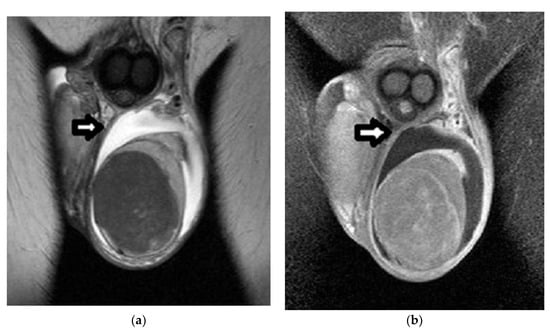

Sertoli-Cell Tumors

- Drevelengas, A.; Kalaitzoglou, I.; Destouni, E.; Skorsalaki, A.; Dimitriadis, A. Bilateral Sertoli cell tumor of the testis: MRI and sonographic appearance. Eur. Radiol. 1999, 9, 1934. [Google Scholar] [CrossRef]